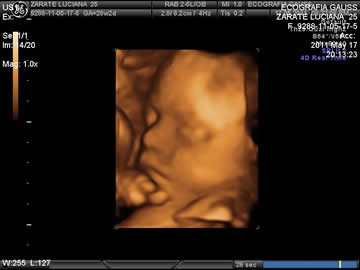

Es un método de ayuda diagnóstica que permite estudiar de una forma distinta la anatomía y fisiología fetal; en donde podrá apreciar a su bebé en tiempo real (en movimiento).

A esta tecnología se le llama 4D porque incorpora la cuarta dimensión que es el tiempo, pudiendo observar las imágenes en movimiento, como sucede en la realidad.

A este ecógrafo se le llama 4D porque muestra imágenes tridimensionales –con volumen- en movimiento de manera simultánea, debido a que esto, se vé en tiempo real.

Esta reconstitución se logra mediante complejas computadoras que traducen la energía emitida en forma del ultrasonido, en imágenes, sin desfase temporal. De esta manera, se obtienen verdaderos videos a color de la vida intrauterina. Además del efecto psico-social que implica para los padres ver a su hijo con tanta claridad, otra ventaja de este equipo es que la energía utilizada es una de las más bajas de las técnicas ultrasonográficas conocidas. Por lo tanto, el impacto sobre el embrión es inocuo.

Permite detectar en gran porcentaje alteraciones anatómicas fetales, dado que muestra planos no visibles con la técnica convencional. Como también, permite a los padres visualizar en forma muy nítida la cara , el cuerpo y sus actividades fisiologicas de su futuro bebé, y se sientan tranquilos de entender las imágenes que en momento de la ecografia se presenta.

Ver un hijo de una manera tan clara y real como un video en el que el pequeño patea, se chupa el dedo, juega con el cordón umbilical y muestra al mundo su sexo sin necesidad de intérpretes, es la maravilla que permite el nuevo equipo